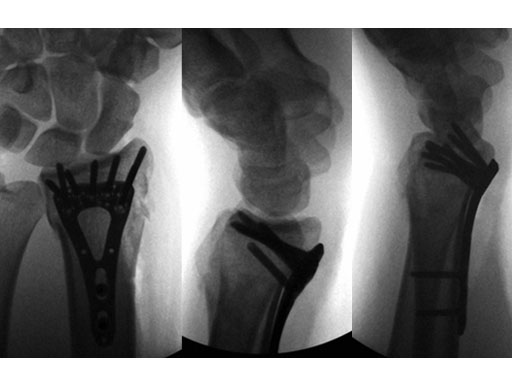

A 26-year-old man suffered a multifragmentary fracture of his left distal radius with extension into the diaphysis (AO23 C3.3) (Fig 1). The VA LCP Extra Long Two-Column plate was used for fixation (Fig 2). After initial immobilization, the plate provided a good postoperative fixation of the fracture.

The fracture showed primary bone healing without callus formation. At the 3-month follow-up, the patient was full weight bearing with excellent clinical function (Fig 3). The radiological follow-up can be technically challenging due to the correct focus of the central ray.

Case 4: Open radius shaft fracture

A 59-year-old farmer suffered a crush injury with an open forearm fracture (AO22 C2, Gustilo and Anderson IIIB) (Fig 1). Initial stabilization was carried out by external fixator (Fig 2). After four rounds of debridement and capillary ingrowth of a splitting skin graft at day 17, the VA LCP Extra Long Two-Column plate was used for fixation of the radius. A 2.7 mm LCP Condylar Plate was used for fixation of the ulna. The plates provided good stability for a functional after-treatment.

At the 3-month follow-up, the patient was full weight bearing with healing fractures (Fig 3).